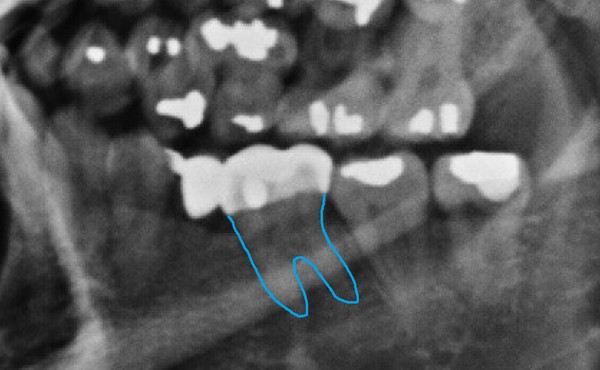

- ▲ 김우현 원장은 박주신씨 명의의 치근단 엑스레이(위)와 자생병원 구외 엑스레이에서 보이는 36번 치아의 아말감 충전형태가 다르게 나타난다고 지적했다. ⓒ 김우현 원장 제공

두 번째로 36번 치아형태도 치근단과 구외 엑스레이가 각각 다르게 나타난다. 치근단 엑스레이에서는 치아뿌리 상부 1/3과 중간 1/3 근원심간 너비가 비슷하다.

다시 말해, 중간부분까지는 좁아지지 않다가 치아 끝부분에 가서야 좁아지는 일반적인 양상을 띠고 있다.치근관의 만곡도 보인다.

하지만 구외 엑스레이에서는 치이뿌리 상부 1/3과 중간 1/3의 근원심간 너비차이가 현격하게 나타나, 치아뿌리 끝으로 갈수록 좁아지는 양상이다. 또 치근단 엑스레이와 달리, 치근관의 만곡이 없다.

반대로 36번 치아 뿌리부분을 보면, 치근단 엑스레이에서는 치근단 병소(apical lesion)가 보이지 않는데, 구외 엑스레이에서는 병소가 관찰된다.

네 번째는 46번 어금니의 원심치근(치아뿌리)이 다르다는 것이다.

박주신 명의의 치근단 엑스레이에서는 정상적으로 치아 뿌리 끝이 가운데를 향해 둥글게 모이는 형태인 반면, 구외 엑스레이는 치아뿌리 끝이 모이지 않고 뒤쪽으로 휘어있는 형태다.

다섯 번째는 하악 구치부의 우상치(taurodontia)다. 우상치는 치수강이 치근단쪽으로 확장된 형태다. 먼저, 치근단 엑스레이에서는 우상치가 보이지 않는다.

그런데 구외 엑스레이는 36, 46, 47, 48번 치아 모두 경증의 우상치 형태를 보이고 있다.